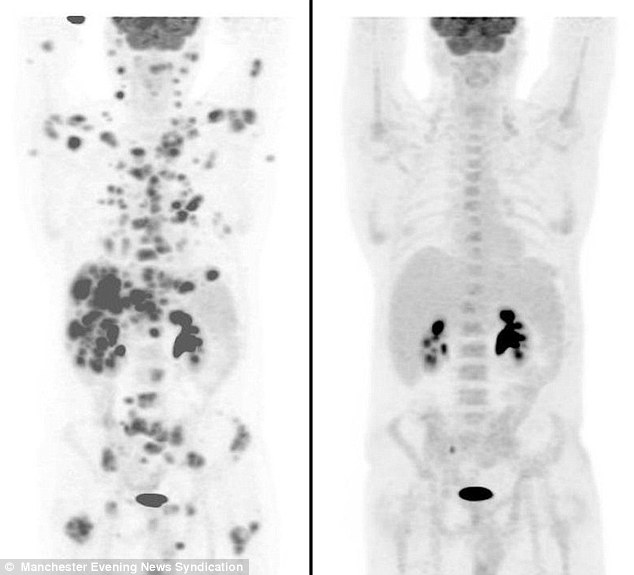

Οι θεραπείες που έκανε το 2001 που πρωτοεμφανίστηκαν καταπολέμησαν αποτελεσματικά τη νόσο, αλλά το 2008 ο καρκίνος του επανεμφανίστηκε πιο επιθετικός παρά ποτέ. Οι εξετάσεις του αποκάλυψαν 60-70 διάσπαρτους όγκους από το κεφάλι έως την κοιλιά του και οι γιατροί του έδωσαν λίγες εβδομάδες ζωής.

Δύο εβδομάδες αργότερα, όμως, οι γιατροί του στο Νοσοκομείο Christie του Μάντσεστερ ανακάλυψαν με έκπληξη ότι το πειραματικό φάρμακο είχε καθαρίσει το σώμα του απ’ όλους τους καρκινικούς όγκους. Η μπρεντουξιμάβη βεδοτίνη (brentuximab vedotin), το φάρμακο που του χορηγήθηκε είναι ένα είδος μονοκλωνικού αντισώματος, το οποίο εγκρίθηκε σε ΗΠΑ και Ευρώπη το 2011 και το 2012 αντιστοίχως.

Σύμφωνα με την daily mail, o γιατρός του είπε ότι οι εξετάσεις του πριν και μετά τη λήψη του φαρμάκου «είναι πιθανώς το πιο εντυπωσιακό σετ εξετάσεων που έχω δει ποτέ».